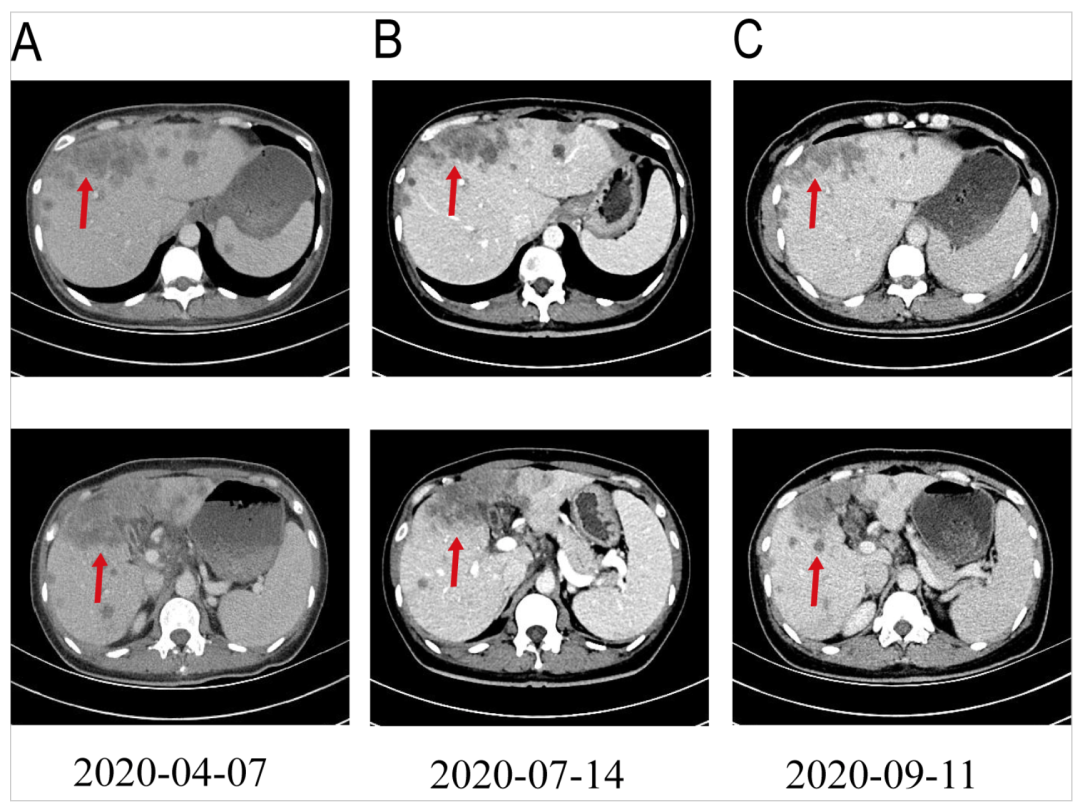

2020年4月17日至2020年8月12日,患者接受了一线6个疗程奥沙利铂(100mg/m2,d1)联合吉西他滨(1000mg/m2,d1和d8)静脉化疗,每3周1次,同时长期口服恩替卡韦胶囊抗乙肝病毒治疗。4程、6程化疗后患者分别行CT复查提示肝内病灶较前减小(Fig2)。